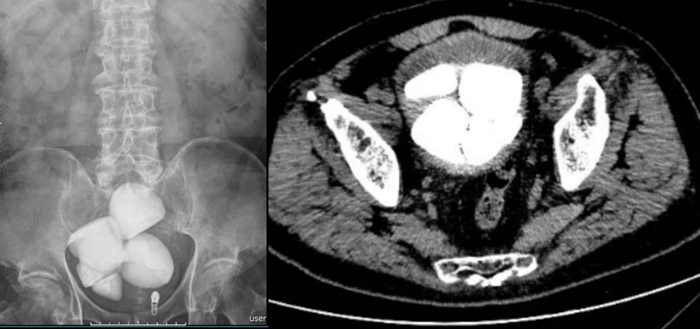

术前的腹部平片及CT检查影像

孔大爷十几年来反复出现尿频、尿急、尿痛,伴肉眼血尿,近1年来症状越来越严重,生活受到很大影响。通过朋友介绍后找到贾灵华求医,入院完善相关检查后确诊为膀胱多发巨大结石。

贾灵华介绍,随着医疗技术的飞速发展,我们现在绝大部分结石手术都可以通过微创手术取出,传统的开放手术已做的非常少。由于多年的尿频尿急排尿困难的折磨,孔大爷身体消瘦、精神不佳,还合并有复杂尿路感染、尿失禁等问题。CT提示患者的结石占据了整个膀胱,结石体量巨大。面对如此复杂、巨大膀胱结石患者,泌尿外科贾灵华团队联合麻醉师、心内科专家一起就手术及麻醉方案进行了详细讨论,同时也进行充分的术前检查和术前准备,做好各类可能出现的意外及救治措施,一致认为不适合微创手术,因为微创手术耗时长,高龄患者身体状况较差,基础疾病较多,身体耐受力差,可能无法耐受如此长时间的麻醉,最终一致同意采取耻骨上膀胱切开取石术,争取以最短时间、最小创伤取出患者的膀胱结石,力求将手术风险降到最低。